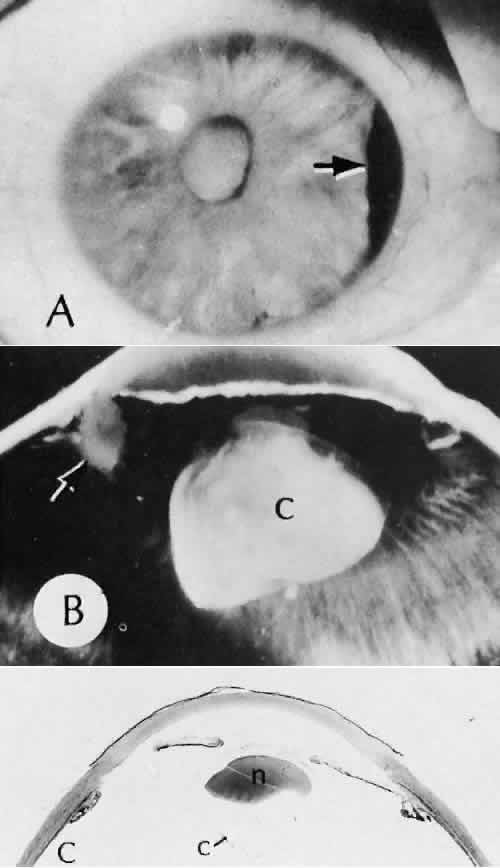

Retinal detachment (Fig. 42) occurs in approximately 2% to 8% of intracapsular cataract surgeries, compared with approximately 0.0013% in the general population. The incidence of retinal detachment after extracapsular cataract extraction and posterior chamber lens implantation ranges between 0.6% and 1.5%.121 Vitreous loss increases the incidence of postoperative detachments, particularly if there is vitreous incarceration into the cataract wound. The character of the retinal detachment is independent of the type of cataract surgery or the type of intraocular lens implanted. However, a lower incidence of proliferative vitreoretinopathy appears in cases of extracapsular cataract extraction than was formerly seen with intracapsular cataract extraction.

Fig. 42. Two cases of retinal detachment following cataract extraction. A. Retinal detachment was identified 4 weeks after cataract extraction. Fixed retinal folds indicate that the situation is inoperable, so no surgical repair was attempted. The anterior chamber angle has become occluded because of neovascularization associated with ischemic retina. B. Retinal detachment was identified 5 weeks after cataract extraction. Two attempts at surgical repair failed. The large equatorial cystic spaces indicated the presence of a scleral-buckling element. The actual material of the sponge and buckle has been lost during tissue processing. The cystic nature of the detached retinal tissue indicates that there was an extended time between the last retinal reattachment attempt and enucleation. In this case, peripheral anterior synechiae are present. The indication for enucleation was most likely a blind painful eye due to secondary glaucoma and reactive uveitis. (Hematoxylin-eosin stain; × 3.)